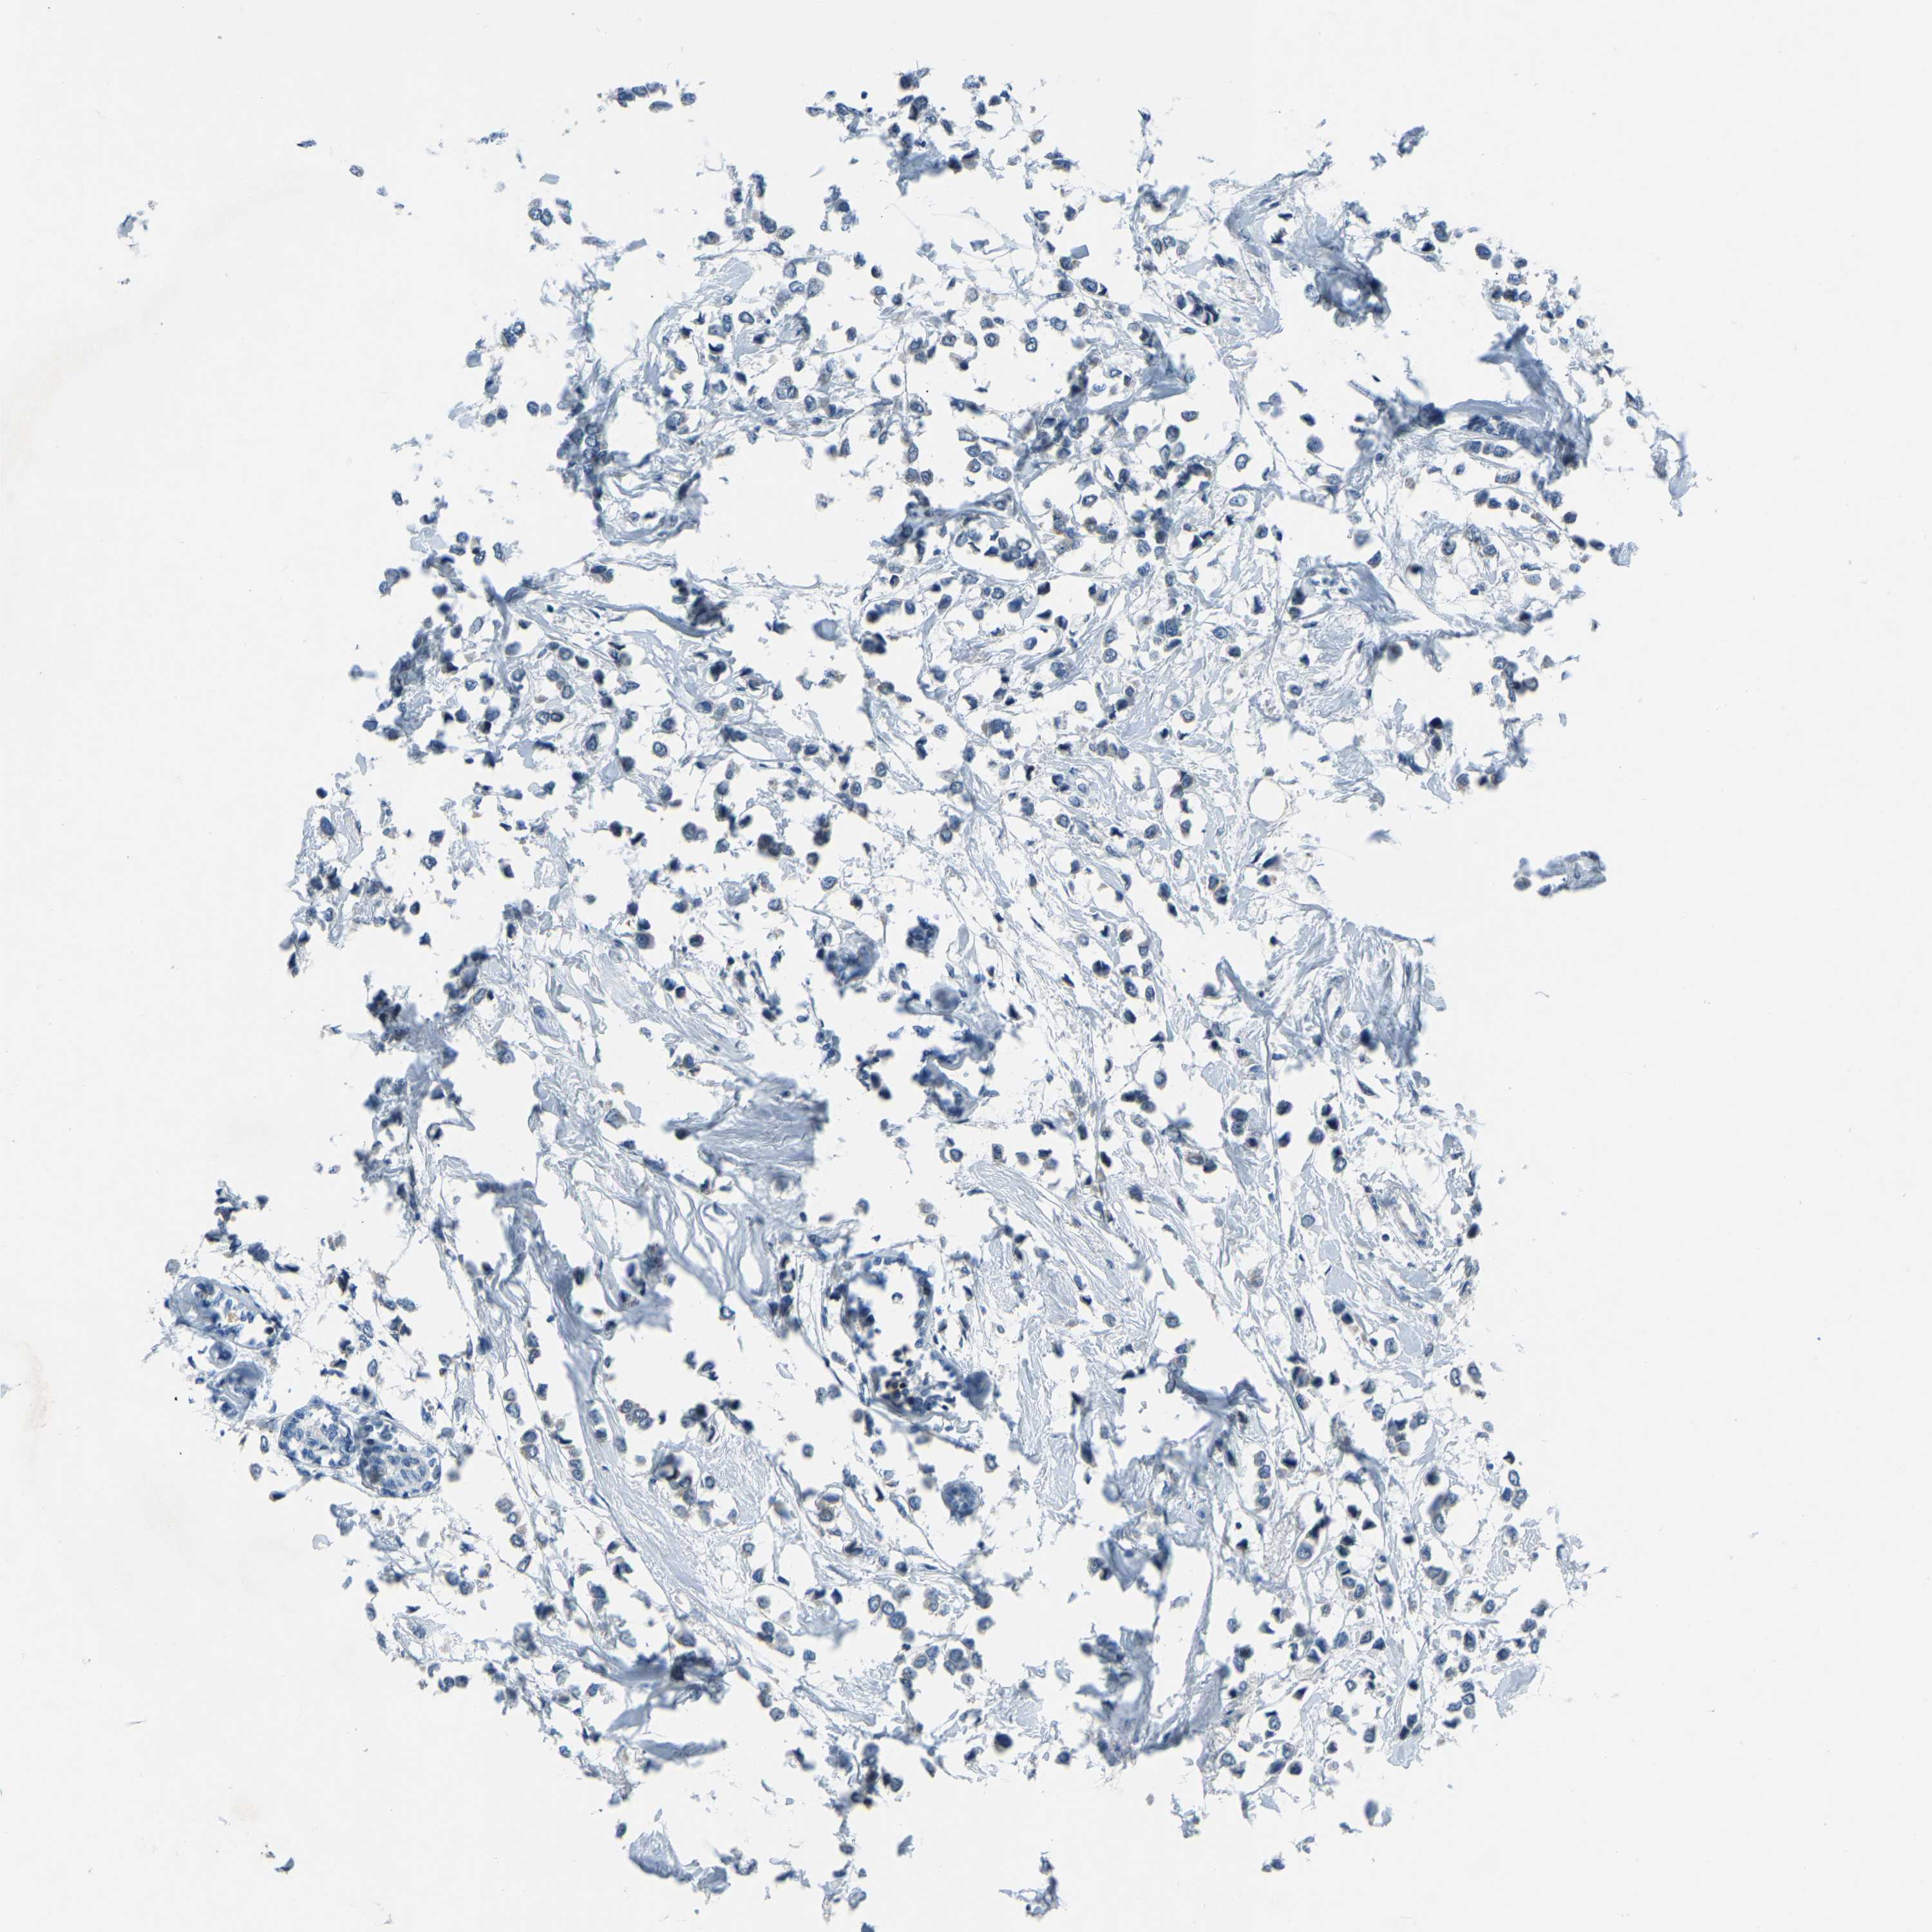

BRCA TCGA BRCA VALIDATION PROTEIN EXPRESSION

Breast cancer

Human cancer